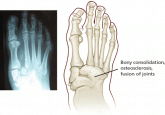

ArticleCharcot neuroarthropathy: An often overlooked complication of diabetesAuthor:Ryan Taylor, DPMPublish date: September 1, 2010Suspect this condition if a patient with long-standing, poorly controlled diabetes and peripheral neuropathy develops a red, hot, swollen foot with...Read More